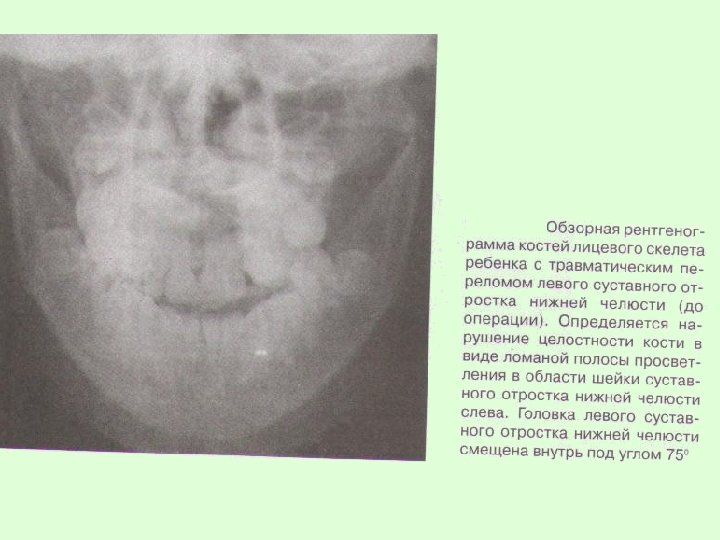

Заключительный диагноз перелома нижней челюсти ставят после проведения рентгенологического исследования в боковой укладке по Генишу или обзорной рентгенограммы нижней челюсти в прямой проекции, при переломе суставного отростка – ортопантомограммы или рентгенограммы сустава по Шуллеру или Парма.

На рентгенограммах обычно определяется нарушение целостности костной ткани, наличие линии перелома, смещение отломков челюсти. В сложных диагностических случаях переломов суставного отростка нижней челюсти у детей для постановки окончательного диагноза при отсутствии явных клинических и рентгенологических признаков используют метод спиральной компьютерной томографии с мультипланарной реконструкцией.